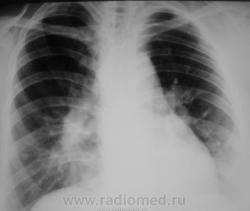

В первую очередь подумал-бы о раке.

А. вот эта "Золушка", помеченная желтой стрелкой, вообще, повергает в уныние...

Может и метастаз. Если сделать томограммы, то может оказаться, что "Золушка" не одна, а много...

Конечно, все может быть, но "саркоидоз", в данном случае, меня как-то не возбуждает...

Очень желательно КТ. Саркоидоз на КТ "разруливается" очень хорошо (легочно-медиастинальная или легочные формы)! Только обязательно пусть сделают КТ с тонким срезом (при саркоидозе весьма характерные очажки!).

Из-за характерных очажков однозначно соглашусь с Валентин Львовичем- саркоидоз тут не возбуждает.

Согласна с Валентином Львовичем.У меня тоже полгода назад сотрудница пришла с увеличенными лимфоузлами корня, сразу же на дообследование направила-оказался саркоидоз, 1 стадия.А здесь округлое образование справа, конечно, подозрительно очень.

За саркоидоз (лёгочно-медиастинальную форму) - очаговые тени в паренхиме имеются.

(-1) При саркоидозе изменения в паренхиме очень вариативны - от единичных чётких очажков до инфильтративных конгломератов!

Обычно по периферии конгломератов если они образуются видны мелкие очажки, что очень хорошо видно на тонкосрезоваой КТ. А вот если сделвать с толстысм срезом (например по 5-10мм), то и конгломераты будут смотрется как обычне инфильтраты. Поэтому я и говорил про тонкосрезовое КТ (заменяет HRCT).

Конечно саркоидоз может выглядеть по разному, но ретикулярный паттерн (встречается в 80% случаев, с признаками нарушения архитектоники, в отличии например от ретикулярного паттерна при канцероматозе + характерные четкоочерченные узелки с перилимфатическим характром распределения (в 60% случаев) - весьма специфическая картина саркоидоза. Консолидации обычно если есть - с наличием по периферии этих мелких узелков - что тоже помогает в диагнозе. Конечно когда процесс уже старый с выраженм фиброзом - все становитсяч сложнее.